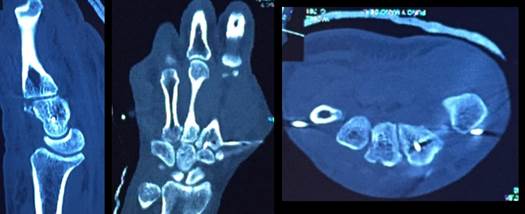

Se realizó reducción cerrada en block quirúrgico con anestesia general, siendo la reducción inestable se colocan agujas de Kirschner del quinto metacarpiano al hueso ganchoso y hueso grande, del segundo al trapezoide y hueso grande y dos desde a base del primer metacarpiano uno al trapecio y otro a la base del segundo. Se controla la reducción y la estabilidad con radioscopia obteniendo buena estabilidad (Figura 3).

Se confecciona además una férula braquipalmar de protección. Se solicitó una tomografía computada de control donde se objetiva buena reducción de las 5 articulaciones carpo-metacarpianas (Figura 4).